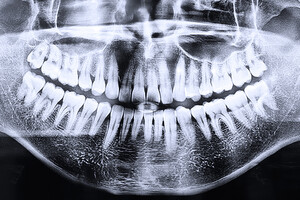

Plaque dentaire : le plus des médecines naturelles

De nombreuses pratiques naturelles permettent d’accéder à un état de santé durable, tant au niveau de la sphère bucco-dentaire qu’au niveau général. Elles peuvent être associées aux recommandations officielles, car elles en augmentent les effets bénéfiques.

Voici quelques bons gestes pour prévenir le développement de la plaque dentaire :